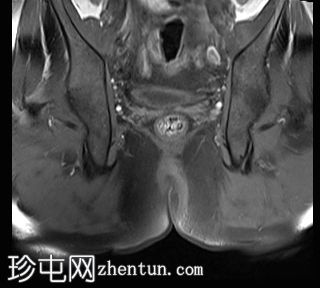

轴向位

T1时间

T1

位于5点钟和6点钟位置之间,在STIR和T2加权图像上呈高信号。

瘘管起源于括约肌间平面附近,穿过肛门内外括约肌,并延伸至左侧坐骨肛门窝。瘘管内充满液体信号,周围有轻微水肿。肛提肌上方未观察到颅骨延伸。

根据圣詹姆斯大学医院的磁共振分类系统,该病例被归类为III级左侧肛周经括约肌瘘,左侧坐骨肛门窝可见炎症改变。